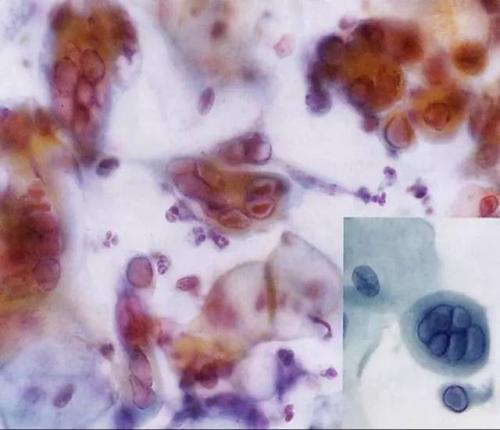

最近,1歲的萌萌(化名)頭上忽然起了一些紅疙瘩,沒過多少天,紅疙瘩竟遍布寶寶全身,讓她奇癢難忍。除螨蟲活動與挖掘隧道疥螨寄生在宿主表皮角質層的深處,以角質組織和淋巴液為食,并以螯肢和前跗爪挖掘,逐漸形成一條與皮膚平行的蜿蜒隧道。隧道最長可達10~15mm。以雌螨所挖的隧道最長,每隔一段距離有小縱向通道通至表皮。雄螨與后若蟲亦可單獨挖掘,但極短,前若蟲與幼蟲則不能挖掘隧道,只生活在雌螨所挖的隧道中。雌螨每天能挖0.5~5mm,一般不深入到角質層的下面。螨蟲怎么治療螨蟲對皮膚的危害:螨蟲在皮膚里面吸取營養成分,刺激毛細血管以及細胞組織,引向皮膚惡化。皮膚螨蟲加速細小皺紋的產生,加速黃褐斑、雀斑、黑斑等色素沉著,還可導致粉刺、痘疤、痤瘡、皮膚粗糙、角質變厚、形成凹凸皮膚。皮膚螨蟲還能形成瘙癢癥、酒糟鼻以及紅臉、紅血絲等。螨蟲怎么治療局部異物反應,引起局部炎性病變。如毛脂器官堵塞,刺激角質層增生,毛囊擴張,毛孔粗大,毛囊營養不足,毛發脫落等病變。皮脂過度分泌,導致油光滿面。家人趕緊將她送到兒童醫院檢查,才發明;禍首禍首;竟是棉被里的螨蟲。專家提示,要想防螨蟲叮咬,要多開窗通風,不給螨類成長的機會;棉被在用之前要晾曬。據萌萌的母親徐女士介紹,2周前,萌萌頭上開端冒紅疙瘩,隨后頭、臉、手到處都長出了紅疙瘩。她嚇得趕緊帶著女兒到兒童醫院檢查。該院皮膚科副主任羅曉燕診斷后發明,患兒的每個紅疙瘩都有綠豆大小,晶瑩透亮,皰頂有一針尖大小的雀斑,水皰的基底部皮膚鮮紅,初步判斷寶寶患的應是丘疹性蕁麻疹,患病的起因可能是被棉被里的螨蟲叮咬所致。羅曉燕表示,螨蟲是一種肉眼看不見的小蟲子,平時愛;埋伏;在被子、枕頭、地毯、布藝沙發、草席上。每個人對螨蟲的過敏水平不同,一些對螨蟲過敏的人,受到螨蟲叮咬,就輕易過敏,并產生紅疙瘩。據理解,幼嬰跟兒童是螨蟲過敏癥狀極為重大的群體,他們皮膚嬌嫩,很輕易對螨蟲有過敏反應。10%的13到14歲的兒童患有塵螨過敏性鼻炎。當你家寶寶在初秋季節皮膚呈現皮疹,奇癢無比,甚至開端一直打噴嚏、流鼻涕,重大者哮喘發生,要警戒誤診為個別感冒咳嗽,可能恰是螨蟲沾染了!羅曉燕提示寬大家長:要想防螨蟲叮咬,首先要堅持環境的衛生;經常晾曬被褥;假如不太陽,可用開水淋燙,等晾干后再利用。